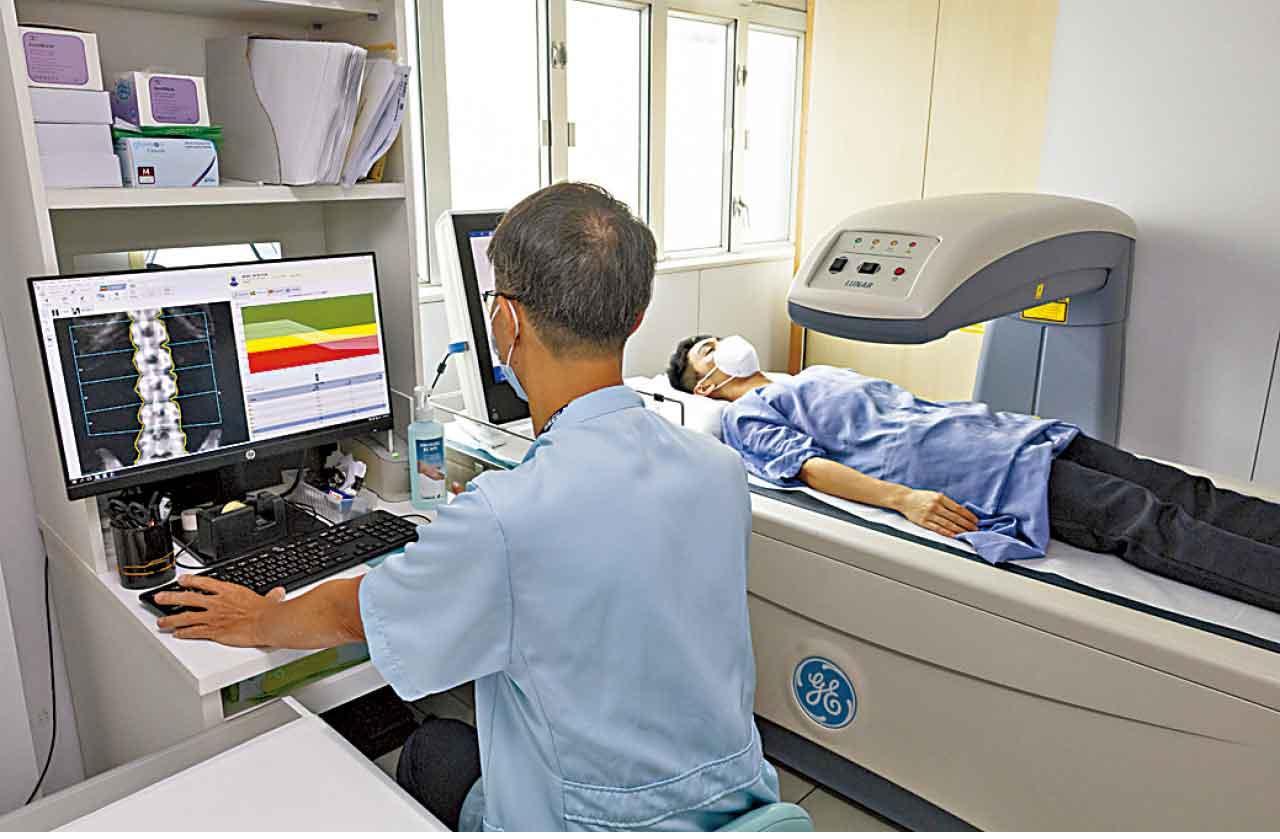

有見老齡化社會需要,醫院推出骨質密度檢查(DEXA)服務。

播道醫院照顧病人無微不至,服務比較個人化(high touch)。但醫院亦要與時並進,借助醫療科技為病人提供針對性的體檢服務,如近年深受歡迎的骨質密度檢查(DEXA),以及判斷肝臟硬度或脂肪程度的肝纖維化掃描檢查,在儀器購置初期亦會以一個非常合宜的價錢提供服務予有需要病人。院長助理Canice補充,「最近醫院放射診斷部試驗引入AI輔助處理影像,結合高運算能力電腦與多元健康數據對照,協助放射診斷部同事更快作出初步診斷,藉此加強服務質素。」而自去年4月起,醫院又為入院部和門診部病人提供專門的傷口護理服務。她表示,手術後病人如處理傷口不當,便會影響康復過程,因此由專科護士提供傷口護理服務,是術後復康的重要一環。